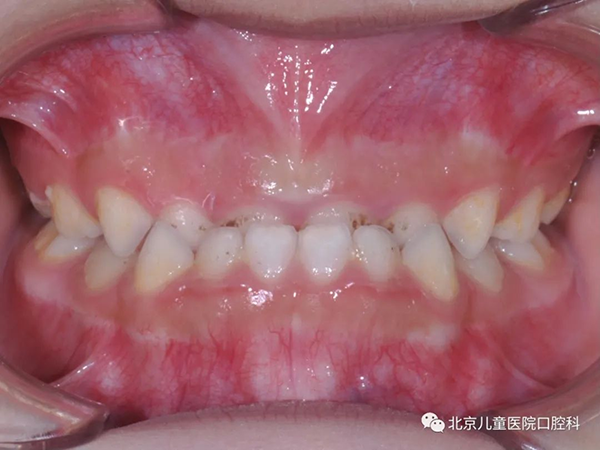

反牙合,也就是我们俗称的“地包天”,这是一种常见的咬合问题。那什么叫“地包天”呢?简单地说,就是当孩子后牙咬住的时候,下牙在上牙的外面。“地包天”不仅影响牙齿健康和颌骨发育,还会影响孩子吃东西、说话等方面的口腔功能,同时还严重影响孩子的面部美观,因此使得“地包天”成为如今最受家长关注的口腔问题之一。那么,孩子的牙齿为什么会形成“地包天”呢?

口腔的局部问题更是“地包天”形成的重要因素。常见的原因包括上颌骨发育不足和下颌骨发育过度;孩子乳牙的小尖牙磨耗不足会造成牙齿早接触而形成“地包天”;上面的乳前牙还没掉恒牙就从里面长出来,和下面的牙齿形成“地包天”;还有后面的大牙变成“虫牙”却没能及时治疗,孩子被迫只能用前牙咀嚼,也会造成下颌骨的前移形成“地包天”。此外,像咬上唇、吐舌头、伸下巴这些口腔不良习惯以及不正确的喂养姿势都有可能造成“地包天”。